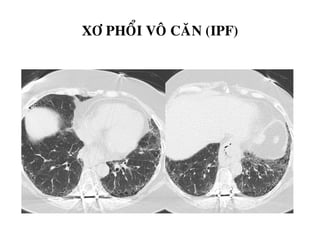

Xơ phổi vô căn (IPF-Idiopathic Pulmonary Fibrosis)

XÔ PHOÅI VOÂ CAÊN (IPF)